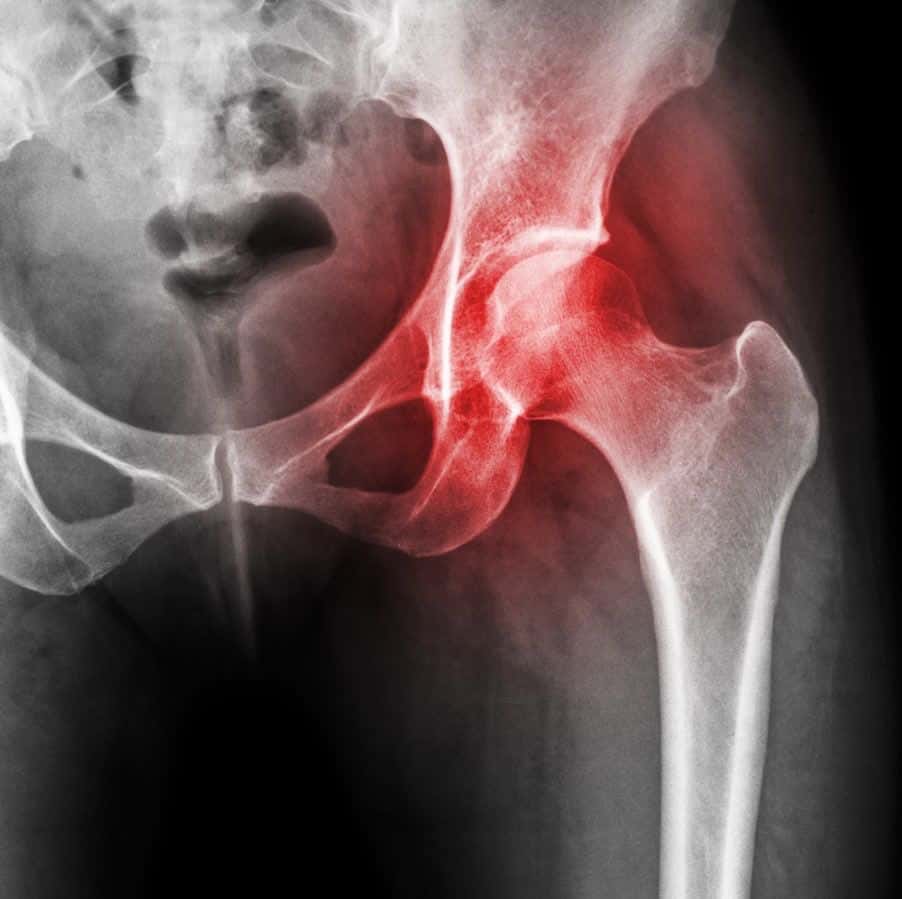

Celecoxib is an NSAID (nonsteroidal anti-inflammatory drug, in the same category as ibuprofen). Like other drugs in this class, it can increase the risk of cardiovascular complications, such as high blood pressure or even a heart attack. Some people would prefer to try nondrug approaches to controlling their arthritis pain. We discuss a number of strategies in our Guide to Alternatives for Arthritis.